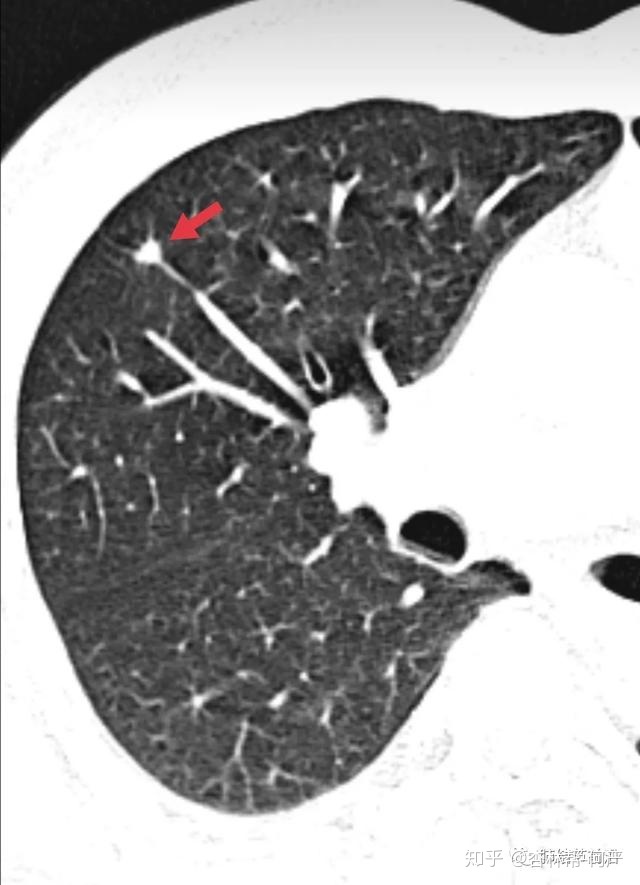

结节3:8mm实性结节,长毛刺,三角形,为良性表现。但是有血管进入,能排除肺癌么?不敢。

结节3:CT值为185,诊断为良性纤维灶结节。